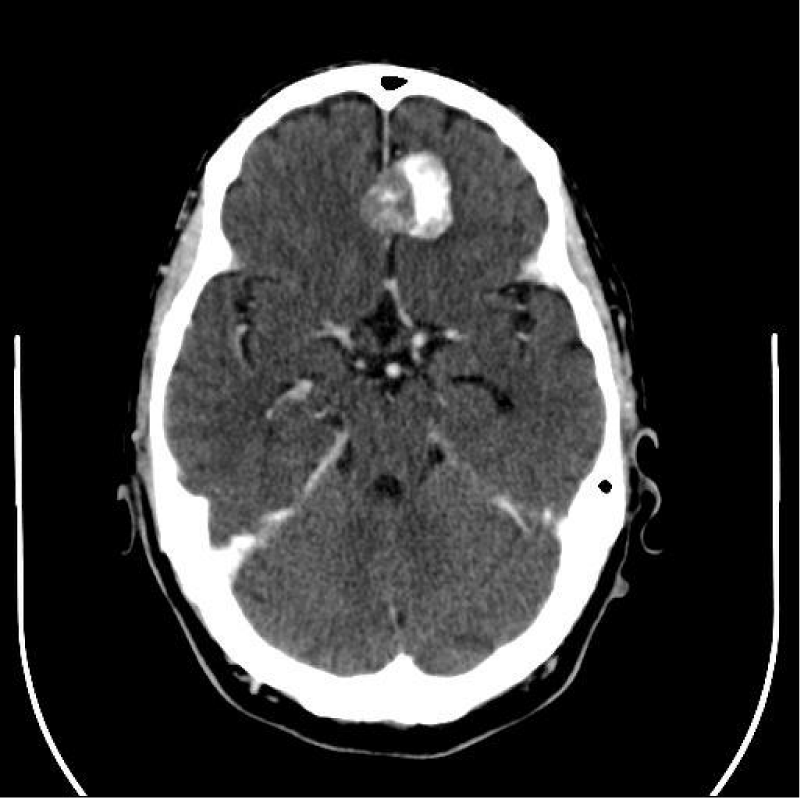

Case 3: Meningioma on 99mTc-HDP bone scan

A 62-aged man referred to 99mTc-byphosphonates bone scintigraphy for the staging of recent diagnosed lung cancer. Concerning the main clinical request, the bone scan whole body image, obtained 2 hours after the i.v. injection of the osteotropic radiopharmaceutical, did not show any pathologic uptake of the tracer in the skeleton, excluding an uptake in L4 vertebrae, potentially due to osteodegeneration. Conversely, focusing on the head region, it was evident a focal area of increased uptake in para-median left frontal area (Figure 3). The man had no previous significant neurologic symptoms in recent anamnesis. Both the locus of this uptake (frontal bone or soft tissues) and the cause of this uptake were unclear, therefore we suggested to perform a complementary morpho-structural examination. The CT scan subsequently performed reported a great meningioma localized in left frontal area, with Calcium deposits included (Figure 4).

Figure 4: Contrast enhanced CT scan of brain showing the calcified and enhancing meningioma, transversal slice. Same case of Figure 3.